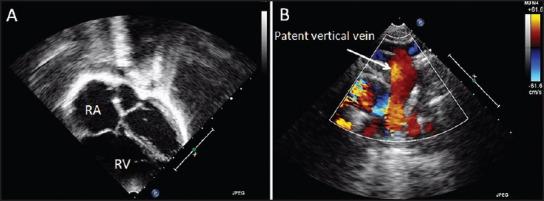

Vertical vein is left patent in some cases of supra-cardiac total anomalous pulmonary venous connection (TAPVC) when there is hemodynamic instability due to noncompliant left atrium and ventricle. After the peri-operative period, this results in features of pre-tricuspid shunt.

Three cases with patent vertical vein following repair of supra-cardiac TAPVC presented with features of pre-tricuspid shunt on follow-up. Trans-catheter closure of patent vertical vein was performed using vascular plug in all three subjects.

The procedure was technically successful in all the patients. There was a complication related to catheter tip breakage in one of them, which was successfully managed. There was no impingement on pulmonary vein in any of the patients.

Patent vertical vein following TAPVC repair results in features of pre-tricuspid shunt. Transcatheter closure of the patent vein is feasible.